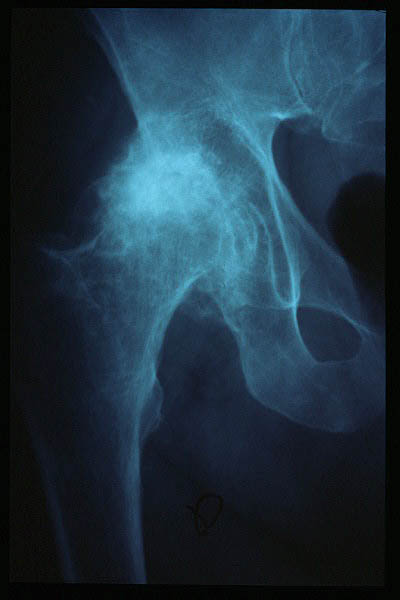

Artrosis avanzada de cadera. Anquilosis.